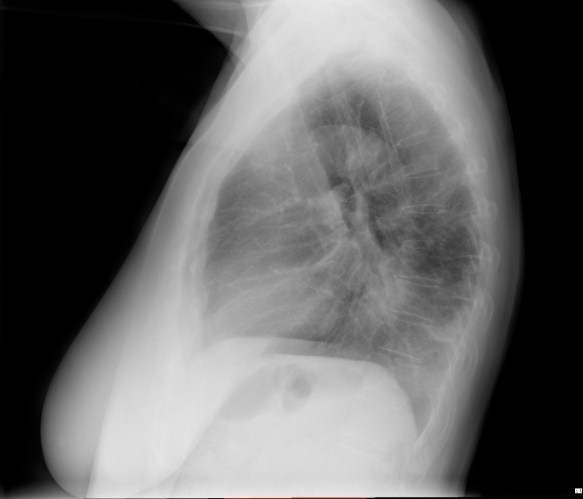

CASO: Febrícula y tos de 4 días de evolución.

Hallazgos:

- En la placa PA se observa una asimetría en los hilios pulmonares, el hilio izquierdo tiene una densidad aumentada.

- Tras examinar la placa lateral se observa un aumento de densidad en la columna que puede ser compatible con una condensación, es el signo de la desnificación vertebral.

SIGNO DE LA DENSIFICACIÓN VERTEBRAL: En la radiografía lateral normal, la densidad de la columna torácica tiende a disminuir desde la parte superior hasta el diafragma; la alteración de ese patrón por la presencia de una densidad superpuesta a la columna, indica la existencia de una consolidación pulmonar. Este signo adquiere especial valor cuando en la proyección posteroanterior la consolidación está oculta en el espacio retrocardíaco o en la base pulmonar.